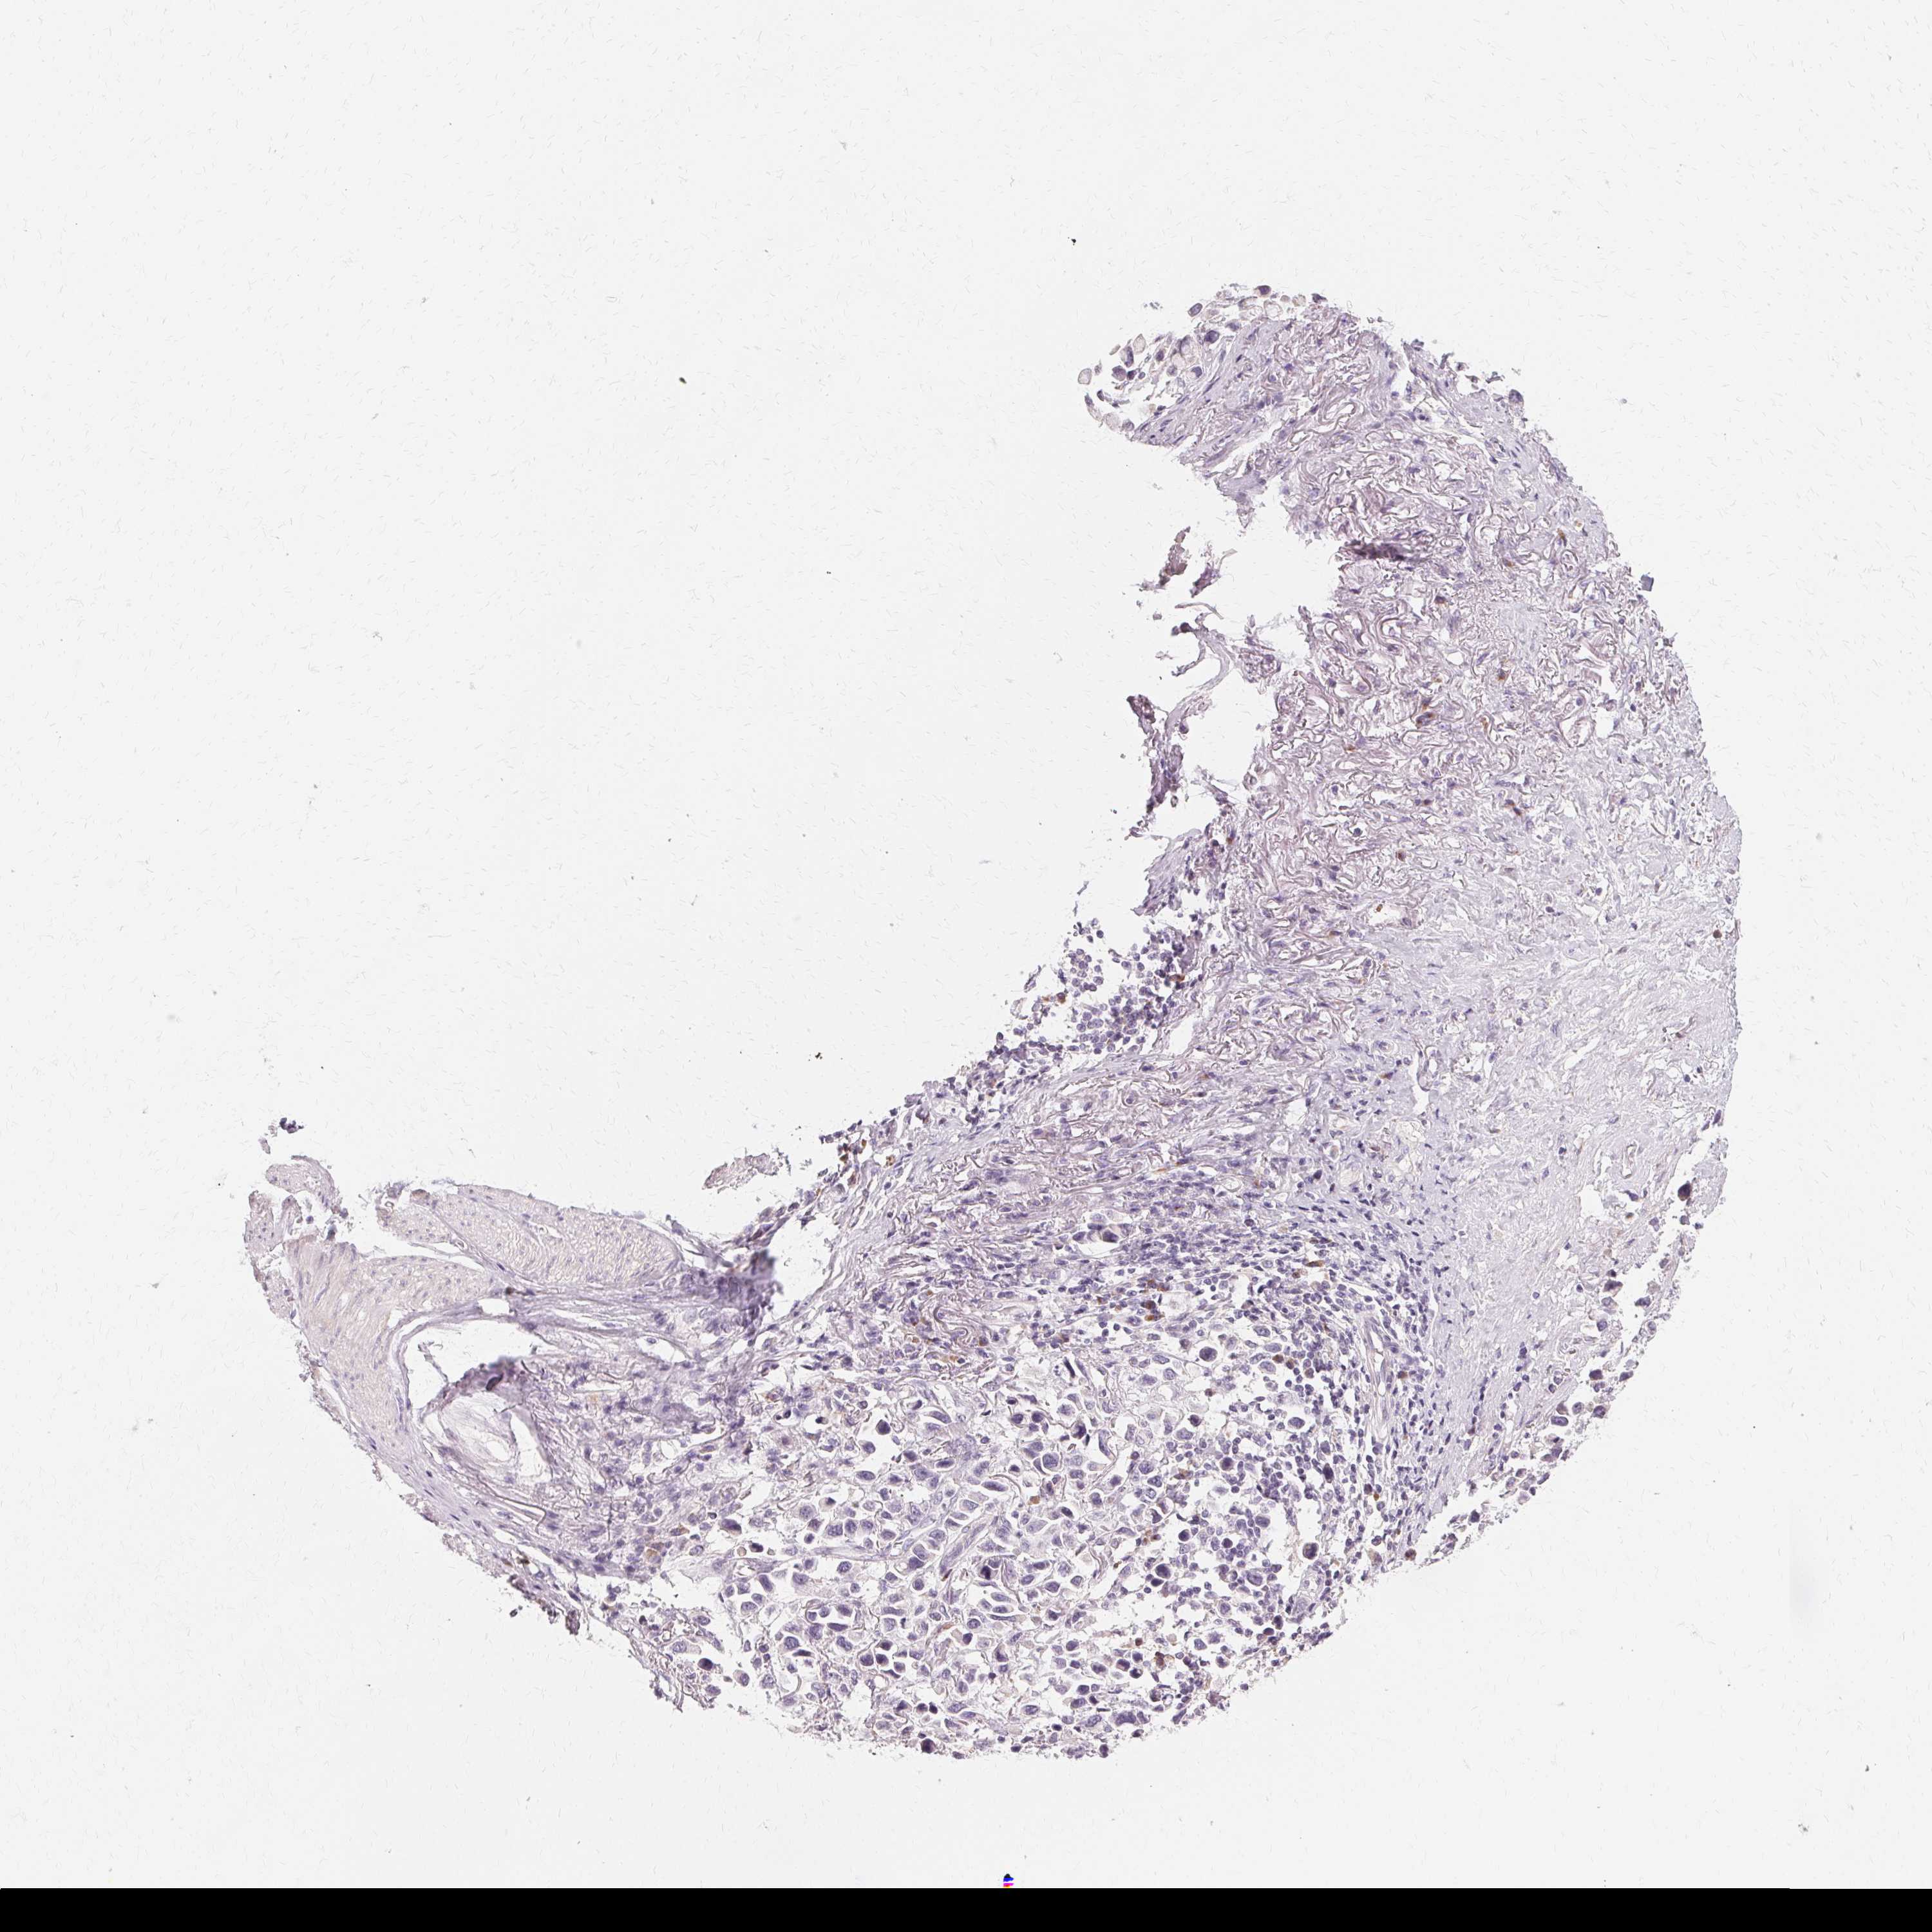

STOMACH CANCER - Protein expressioni

A mouse-over function shows sample information and annotation data. Click on an image to view it in a full screen mode. Samples can be filtered based on level of antibody staining by selecting one or several of the following categories: high, medium, low and not detected. The assay and annotation is described here.

Antibody stainingi

Antibody staining in the annotated cell types in the current human tissue is reported as not detected, low, medium, or high, based on conventional immunohistochemistry profiling in selected tissues. This score is based on the combination of the staining intensity and fraction of stained cells.

Each image is clickable and will lead to virtual microscopy that enables deeper exploration of all samples and also displays staining intensity scores, fraction scores and subcellular localization as well as patient and tissue information for each sample.

Antibody HPA048022

Staining

High

Medium

Low

Not detected

Intensity

Strong

Moderate

Weak

Negative

Quantity

>75%

75%-25%

<25%

None

Location

Nuclear

Cytoplasmic/membranous

Cytoplasmic/membranous,nuclear

Adenocarcinoma, NOS